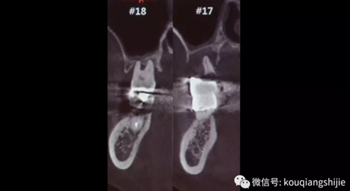

我們可以看到#17,18的牙周炎非常嚴(yán)重

從CT上我們可以看到骨破壞非常嚴(yán)重

拔牙后也將拔牙窩內(nèi)的黏膜提拉上來(lái)

十周之后我們可以看到黏膜組織沒(méi)有出現(xiàn)凹陷

翻瓣之后可以看到形成的充足的骨量